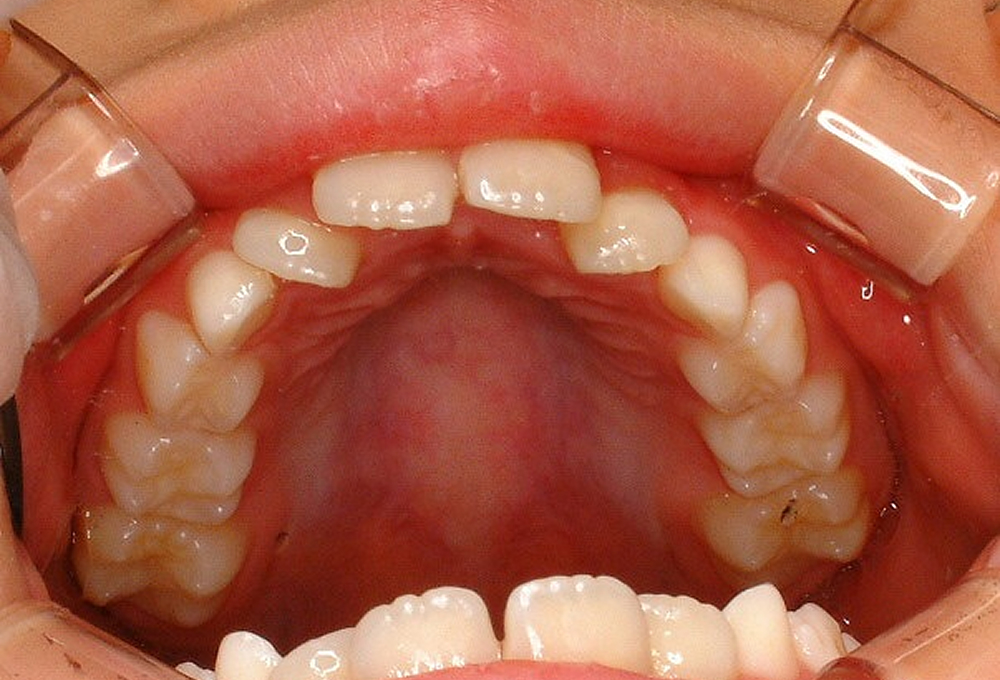

②術前 上顎